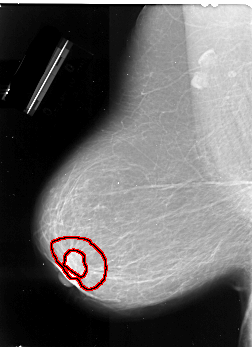

FILE: A_1011_1.LEFT_MLO.OVERLAY

TOTAL_ABNORMALITIES 1

ABNORMALITY 1

LESION_TYPE MASS SHAPE IRREGULAR MARGINS SPICULATED

ASSESSMENT 5

SUBTLETY 4

PATHOLOGY MALIGNANT

TOTAL_OUTLINES 2

BOUNDARY

CORE